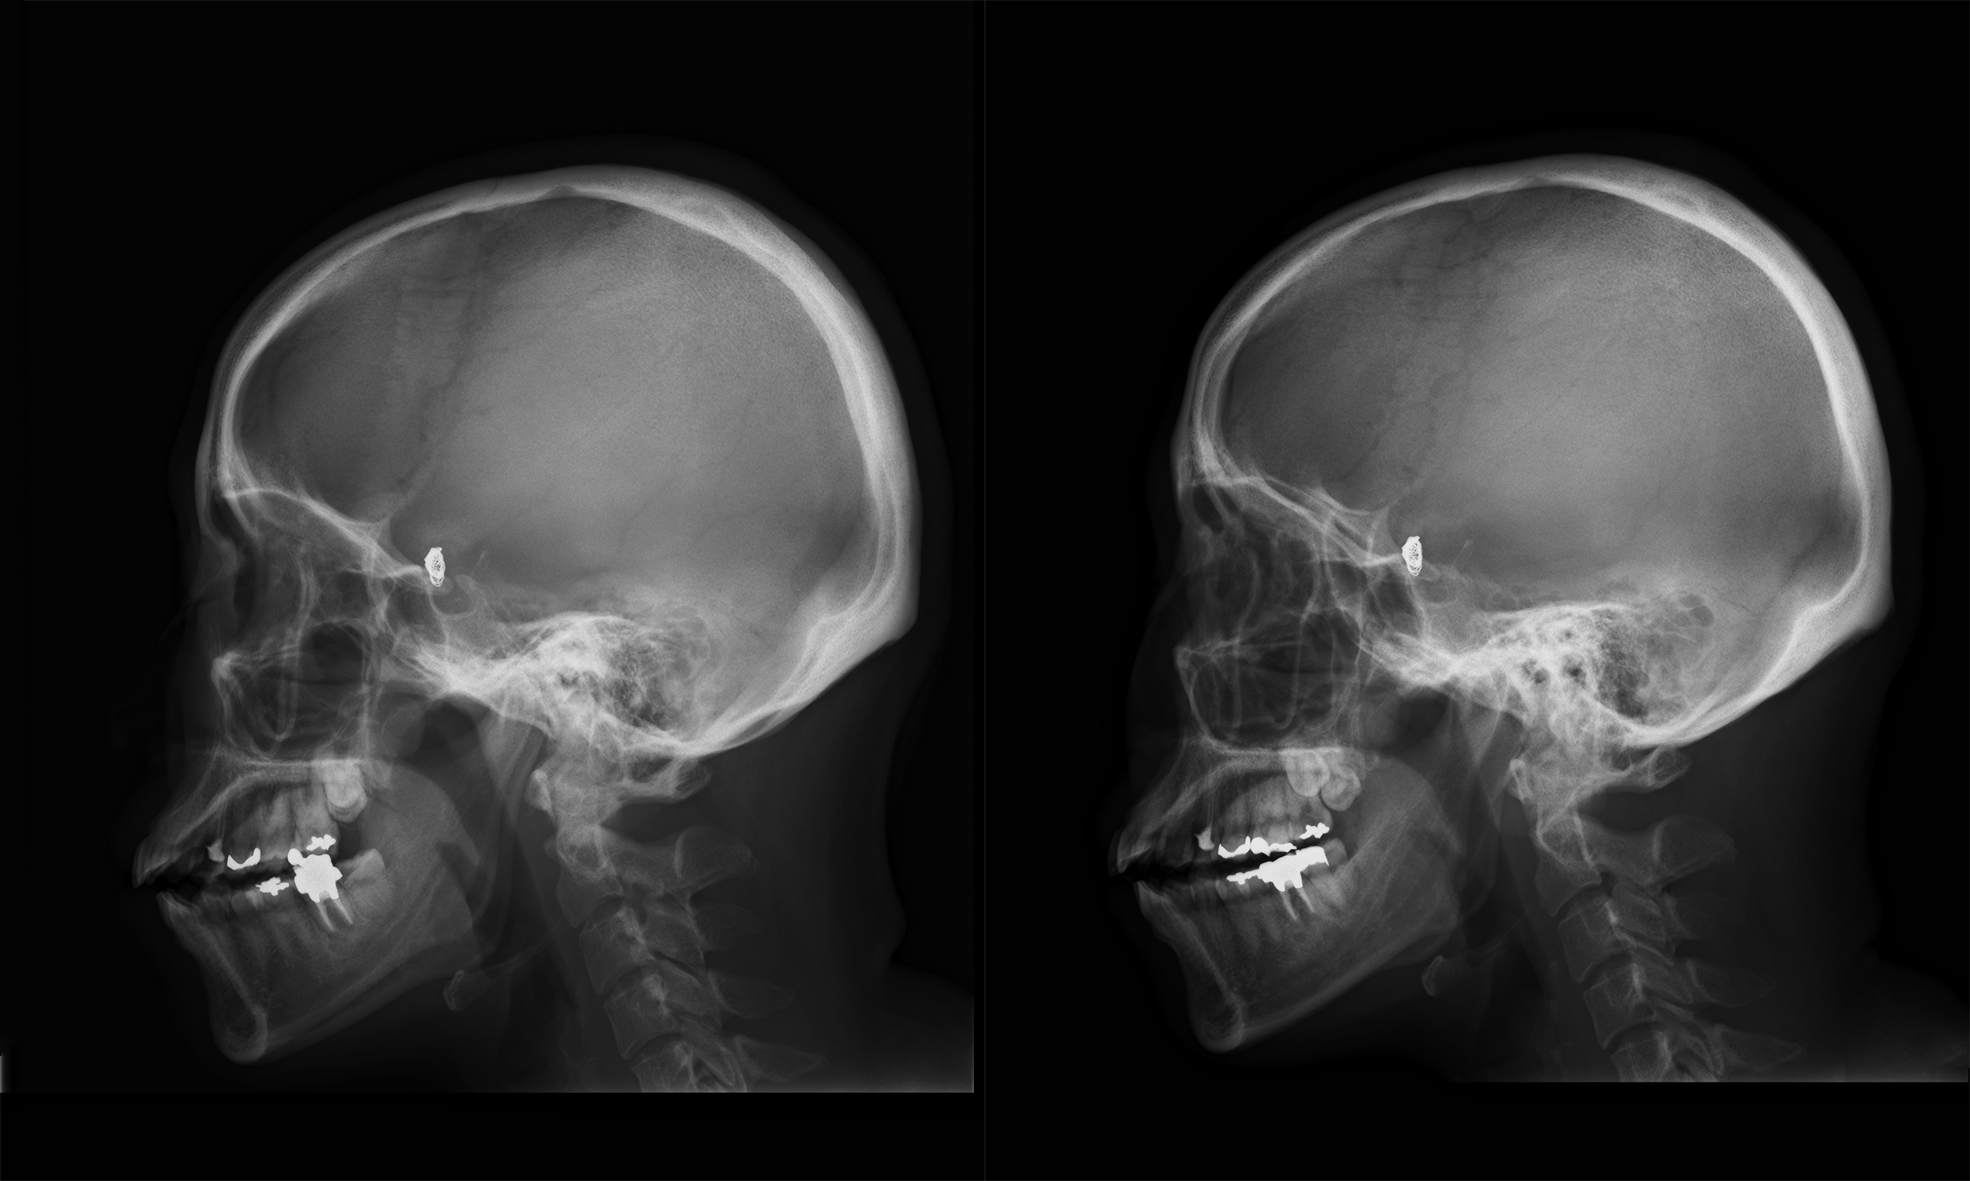

体の撮影したい部位にX線を照射し、体を透過したX線を画像に変換することで肉眼的に体の異常を見つけることができます。

胸部・腹部の画像は心臓や肺、腸などの臓器の状態の観察に役立ちます。骨の画像は骨折や骨腫瘍などの有無、関節炎やリウマチ疾患などの診断に有用です。

以前はフィルムを現像していたので画像がみられるようになるまで時間がかかっていましたが、現在ではデジタル化によってすぐに撮影した画像を確認できるようになり検査時間が短縮されています。(下図の頭部画像は立体視(ステレオグラム)できます)